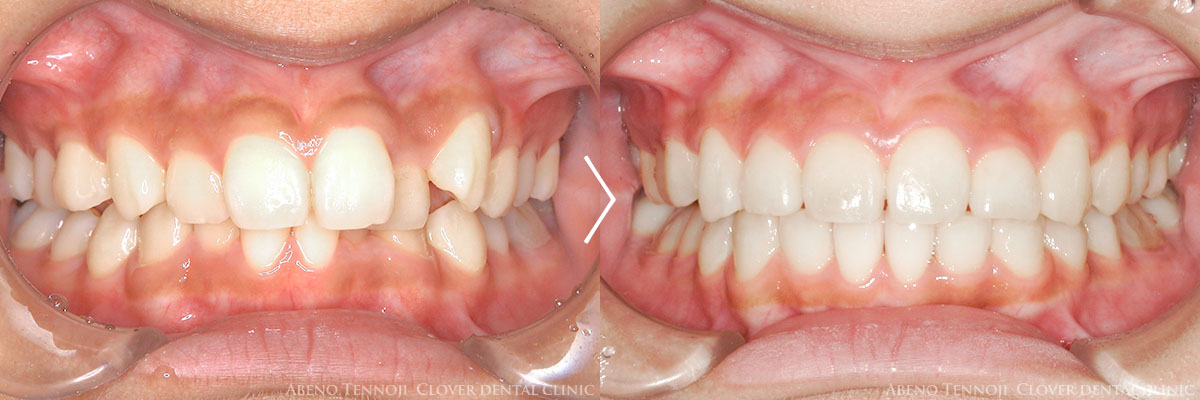

当法人では、インビザラインの多くの実績があります。その実績から、マウスピース矯正のクオリティには自信を持っております。

実はマウスピース矯正にも、様々なレベルがあります。同じインビザラインでもそうです。

実績に裏打ちされた、確実な技術をお約束します。安心の中でのインビザラインを、ぜひおすすめ致します。